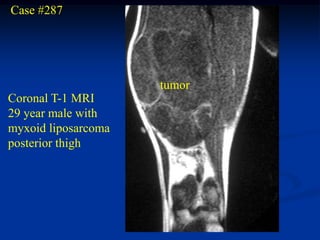

Case #287

tumor

Coronal T-1 MRI

29 year male with

myxoid liposarcoma

posterior thigh

Axial PD MRI

Axial T-2 MRI

Wide resection specimen

Photomic showing numerous vascular channels

Case #287 tumor Coronal T-1 MRI 29 year male with myxoid liposarcoma posterior thigh

• 198.

• 199.

• 200.

• 201.

Photomic showing numerousvascular channels